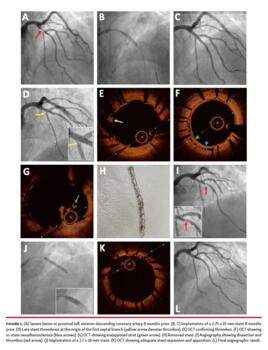

A 62-year-old man presented with unstable angina 8 months earlier. The patient underwent percutaneous coronary intervention (PCI) of the proximal left anterior descending coronary artery with a 2.75 x 15 mm cobalt-chromium sirolimus-eluting stent (Biotronik AG) (Figures 1A-1C). The patient was discharged uneventfully on aspirin and clopidogrel.

Eight months later, the patient was admitted for non-ST segment elevation myocardial infarction (STEMI). Coronary angiography showed late stent thrombosis at the origin of the first septal branch (Figure 1D), probably due to turbulent flow at the level of the septal and diagonal branches and proximal stent malapposition. Optical coherence tomography (OCT) confirmed the presence of thrombus (Figure 1E) and showed in-stent neoatherosclerosis (Figure 1F). Unfortunately, the guidewire was probably advanced through a proximal malapposed stent strut (Figure 1G). Proximal reference lumen diameter (RLD) was 4 mm and distal RLD was 2.70 mm. When removing the OCT catheter, certain resistance was felt due to device entrapment. Small forward-backward movements were unsuccessful to achieve OCT catheter release. Continuous soft traction on both the OCT catheter and guidewire was performed to achieve removal of the system. When the OCT catheter was retrieved, it was found that the stent implanted 8 months earlier had been completely removed over the OCT catheter (Figure 1H). Angiography showed dissection and thrombus (Figure 1I). PCI was performed with a 2.75 x 26 mm cobalt-chromium zotarolimus-eluting stent (Medtronic) that was implanted at 12 atm with optimal stent expansion and apposition after postdilation and proximal optimization technique with a 4 x 8 mm non-compliant balloon for mismatched lesion (Figures 1J-1L). The patient was discharged uneventfully on aspirin and prasugrel.